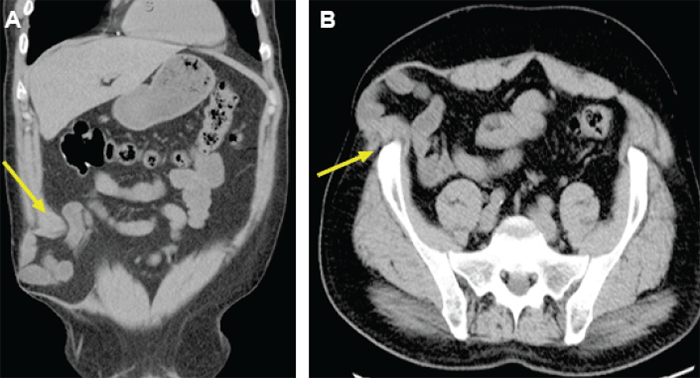

In the first case, the patient, a 68-year-old man, underwent robotic-assisted sigmoid colectomy for diverticulitis three years prior to presenting to our clinic. Subsequently, he developed an incisional hernia and underwent robotic TAR ventral hernia repair with mesh. A more complex, recurrent hernia then developed. Preoperative CT scan showed herniation of bowel above the posterior sheath and mesh with a partial division of the semilunar line on the right side, disconnecting the internal oblique from the rectus complex (Figure 1). There was also a partial division of the left semilunar line with retraction of the internal oblique. Repair would require reconstruction of the internal oblique and rectus complex.

Figure 1. Preoperative CT Scans, Case 1. Published with Permission

A) Recurrent ventral hernia causing partial division of left semilunar line and retraction of internal oblique muscle; B) sagittal view